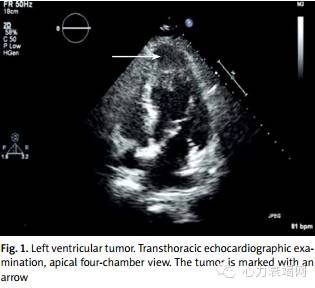

该患者是肥胖女性,61岁,既往有高血压病史,同时使用CPAP治疗阻塞性睡眠呼吸暂停。病史包括使用ACEi类药物治疗高血压时发生血管神经性水肿。从2004年开始,患者开始接受原发于子宫的平滑肌肉瘤的治疗,患者接受了数次外科手术。外科手术后行了放了和化疗的补充治疗。之后该患者因超声发现心脏中午于心脏专科医院接受治疗。肿物大小约35*35mm占据了左心室的顶部(见图1)。

该患者是因运动耐力逐渐恶化症状,然后接受了心脏病诊断。随后即接受了外科治疗。手术切除了左室壁肿物(3*3cm)。术后由于发生了低心输出量(EF26%),需要使用儿茶酚胺,同时因缓慢性心律失常使用了临时心脏起搏器,使得在监护室内时间延长。术后15天(图2.3)患者转入心脏病医院。体格检查如下:血压 135/85mmHg,心率100次/分,双肺底啰音,下肢水肿。随后患者接受了心衰治疗。因既往有使用ACEi类药物引起的血管神经性水肿,故此次未给予该类药物治疗。超声随访EF值从26%上升至30%。药物治疗稳定了患者的症状。同时因患者已行根治性手术,故无需行放化疗。3月后超声示EF值提升至38%。12月后随访LVEF值40%,同时未见新发肿物。